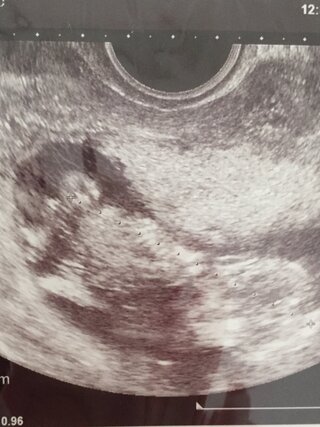

そして、胎児が成長してくると、 陰茎の根本に陰嚢が2つ確認できる ようになります。 女の子は陰茎のような目立つ外性器がないので判定が難しいのですが、 太ももの間に木の葉やコーヒー豆のような大陰唇が見え ます。しかしその一方で、8カ月になる胎児を宿していた妊婦の標本も展示するなど、世界各地で物議を醸しているのも事実だ。 このように人体標本が多方面で物議を醸している状況下、中国のサイト上に、切り取られたと思しき 女性器 の解剖標本が掲載された。しかしその一方で、8カ月になる胎児を宿していた妊婦の標本も展示するなど、世界各地で物議を醸しているのも事実だ。 このように人体標本が多方面で物議を醸している状況下、中国のサイト上に、切り取られたと思しき 女性器 の解剖標本が掲載された。

19週で判明!胎児の体勢によるかも 上の子は男の子ですが、はっきり言われたのは7ヶ月の時でした。 それまでなぜか検診の時は横向きとかだったんですよね。 下の子は女の子でしたが、19週で4dで診てもらった時、先生に「女の子だね!」と断言されました。そして、胎児が成長してくると、 陰茎の根本に陰嚢が2つ確認できる ようになります。 女の子は陰茎のような目立つ外性器がないので判定が難しいのですが、 太ももの間に木の葉やコーヒー豆のような大陰唇が見え ます。